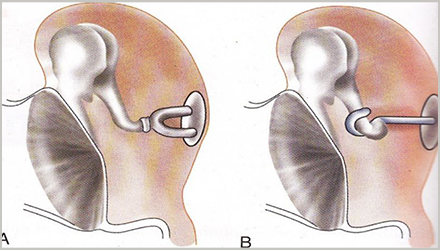

2.镫骨切除术

正如动脉粥样硬化会引起动脉硬化一样,耳硬化指的是中耳镫骨底板上出现了异常硬化,从而出现听力下降。

目前耳硬化症的治疗方法主要是手术,其中镫骨切除术是公认的治疗方法:

将出现异常硬化的镫骨部分或全部切除,用自体的残余镫骨,或自体其它处的骨或软骨小柱、各种有机无机材料制成的人工镫骨,置于砧骨长突与前庭窗之间代替镫骨。